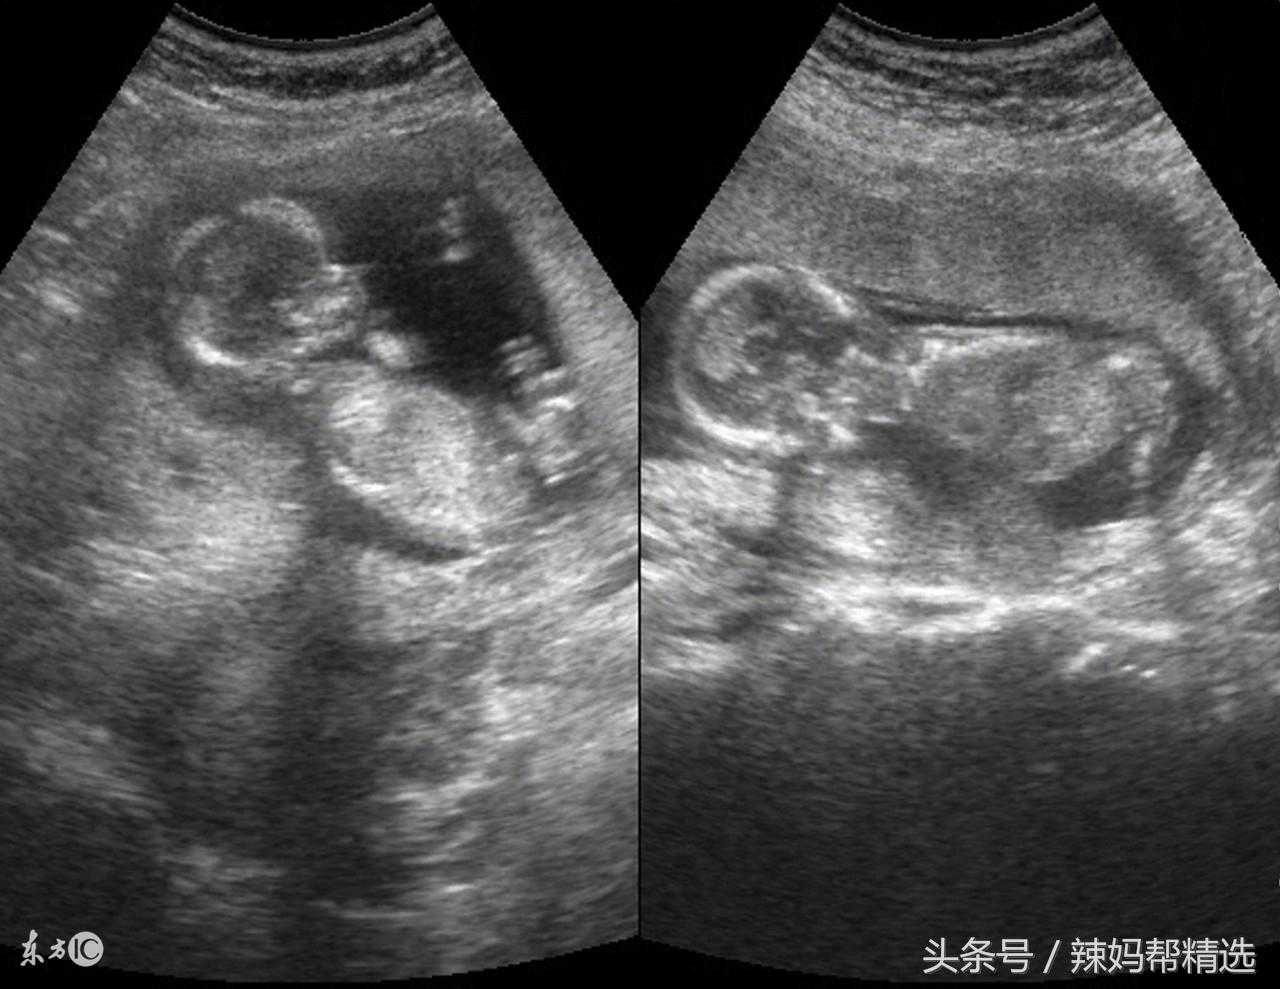

四维彩超是超声检查的一种,除了一般彩超的功能外,还可以进行胎儿头面部立体成像,可清晰地显示眼、鼻、口、下颔等状态,可协助医生直接对胎儿先天畸形进行诊断,包括表面畸形、内脏畸形和头面部畸形,能确定胎儿在子宫中的精确位置。

四维超声能准确地分辨出胎儿的性别四维超声同其它超声检查相比,可以实时观察人体内部器官的动态运动,也能准确地分辨出胎儿的性别。

四维彩超检查最佳时间为怀孕6~8个月(26~32周),这时的宝宝各方面都基本发育完成,做四维彩超检查能有效排查宝宝出现发育畸形的情况。

四维彩超可以在检查胎儿时实现多方位和多角度观察,从而准确地反映出胎儿真实的生长和发育情况。